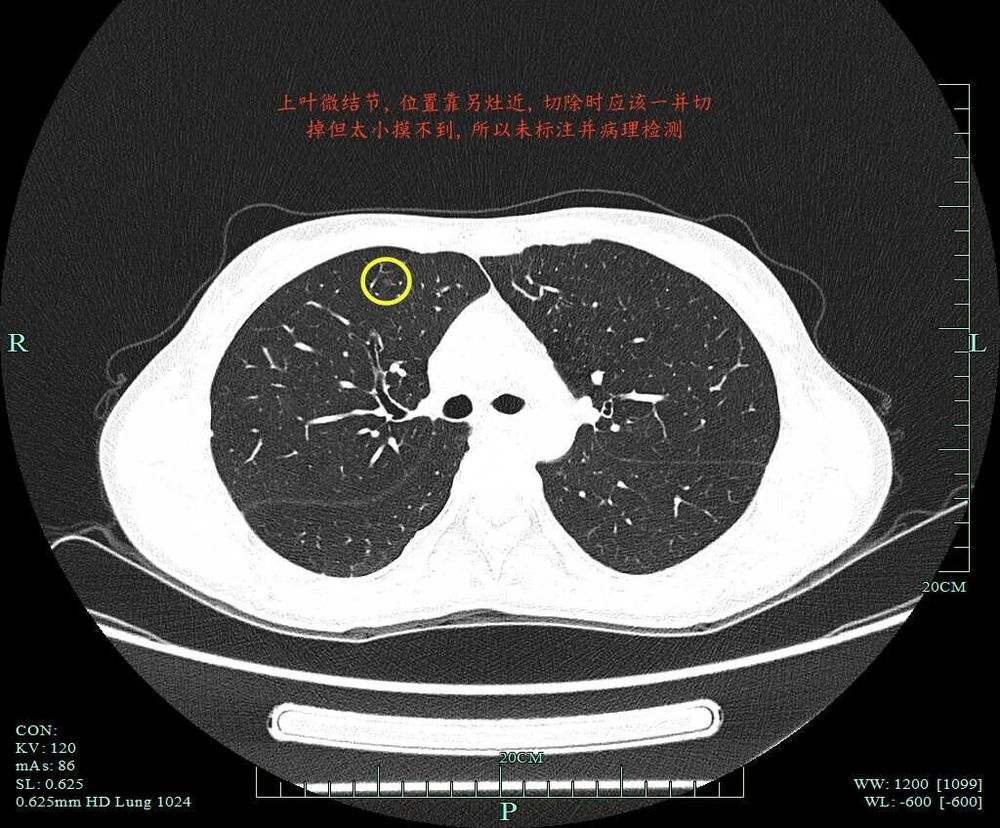

指南上说优先处理主病灶,兼顾次病灶,在不影响生存及符合无瘤原则前提下尽量切除病灶并尽可能保留肺功能。次病灶若是纯GGO,受限于心肺功能无法全部切除时,建议6-12个月随访1次。也就是说:如果心肺功能吃得消,即便次病灶是纯GGO,也是应该尽量切除。这个原则也是宣扬“一网打尽”处理肺结节的医生的指导性原则。但我总觉得指南也是人定的、脱胎于临床研究与回顾分析得出的结论肯定会落后于疾病的发展与时代的变化、疾病谱的改变,从而不一定适应临床。死守指南会导致患者肺功能受损明显、创伤太大、费用过高,而且无法解决导致多发病灶的机体内环境与外环境因素,从而难以避免后续随访中再检出新的病灶。所以我一直宣扬“抓大放小”。今天分享的这个病例右侧较为明显的有四处病灶,主病灶A在右下叶靠近叶间裂,次病灶一处在右上叶病灶B,一处在右下病灶C,还有一处密度很淡的病灶D是邻近病灶B的。我们是如何决策与考虑的?

上叶病灶D邻近病灶B,但太微小,也很淡。